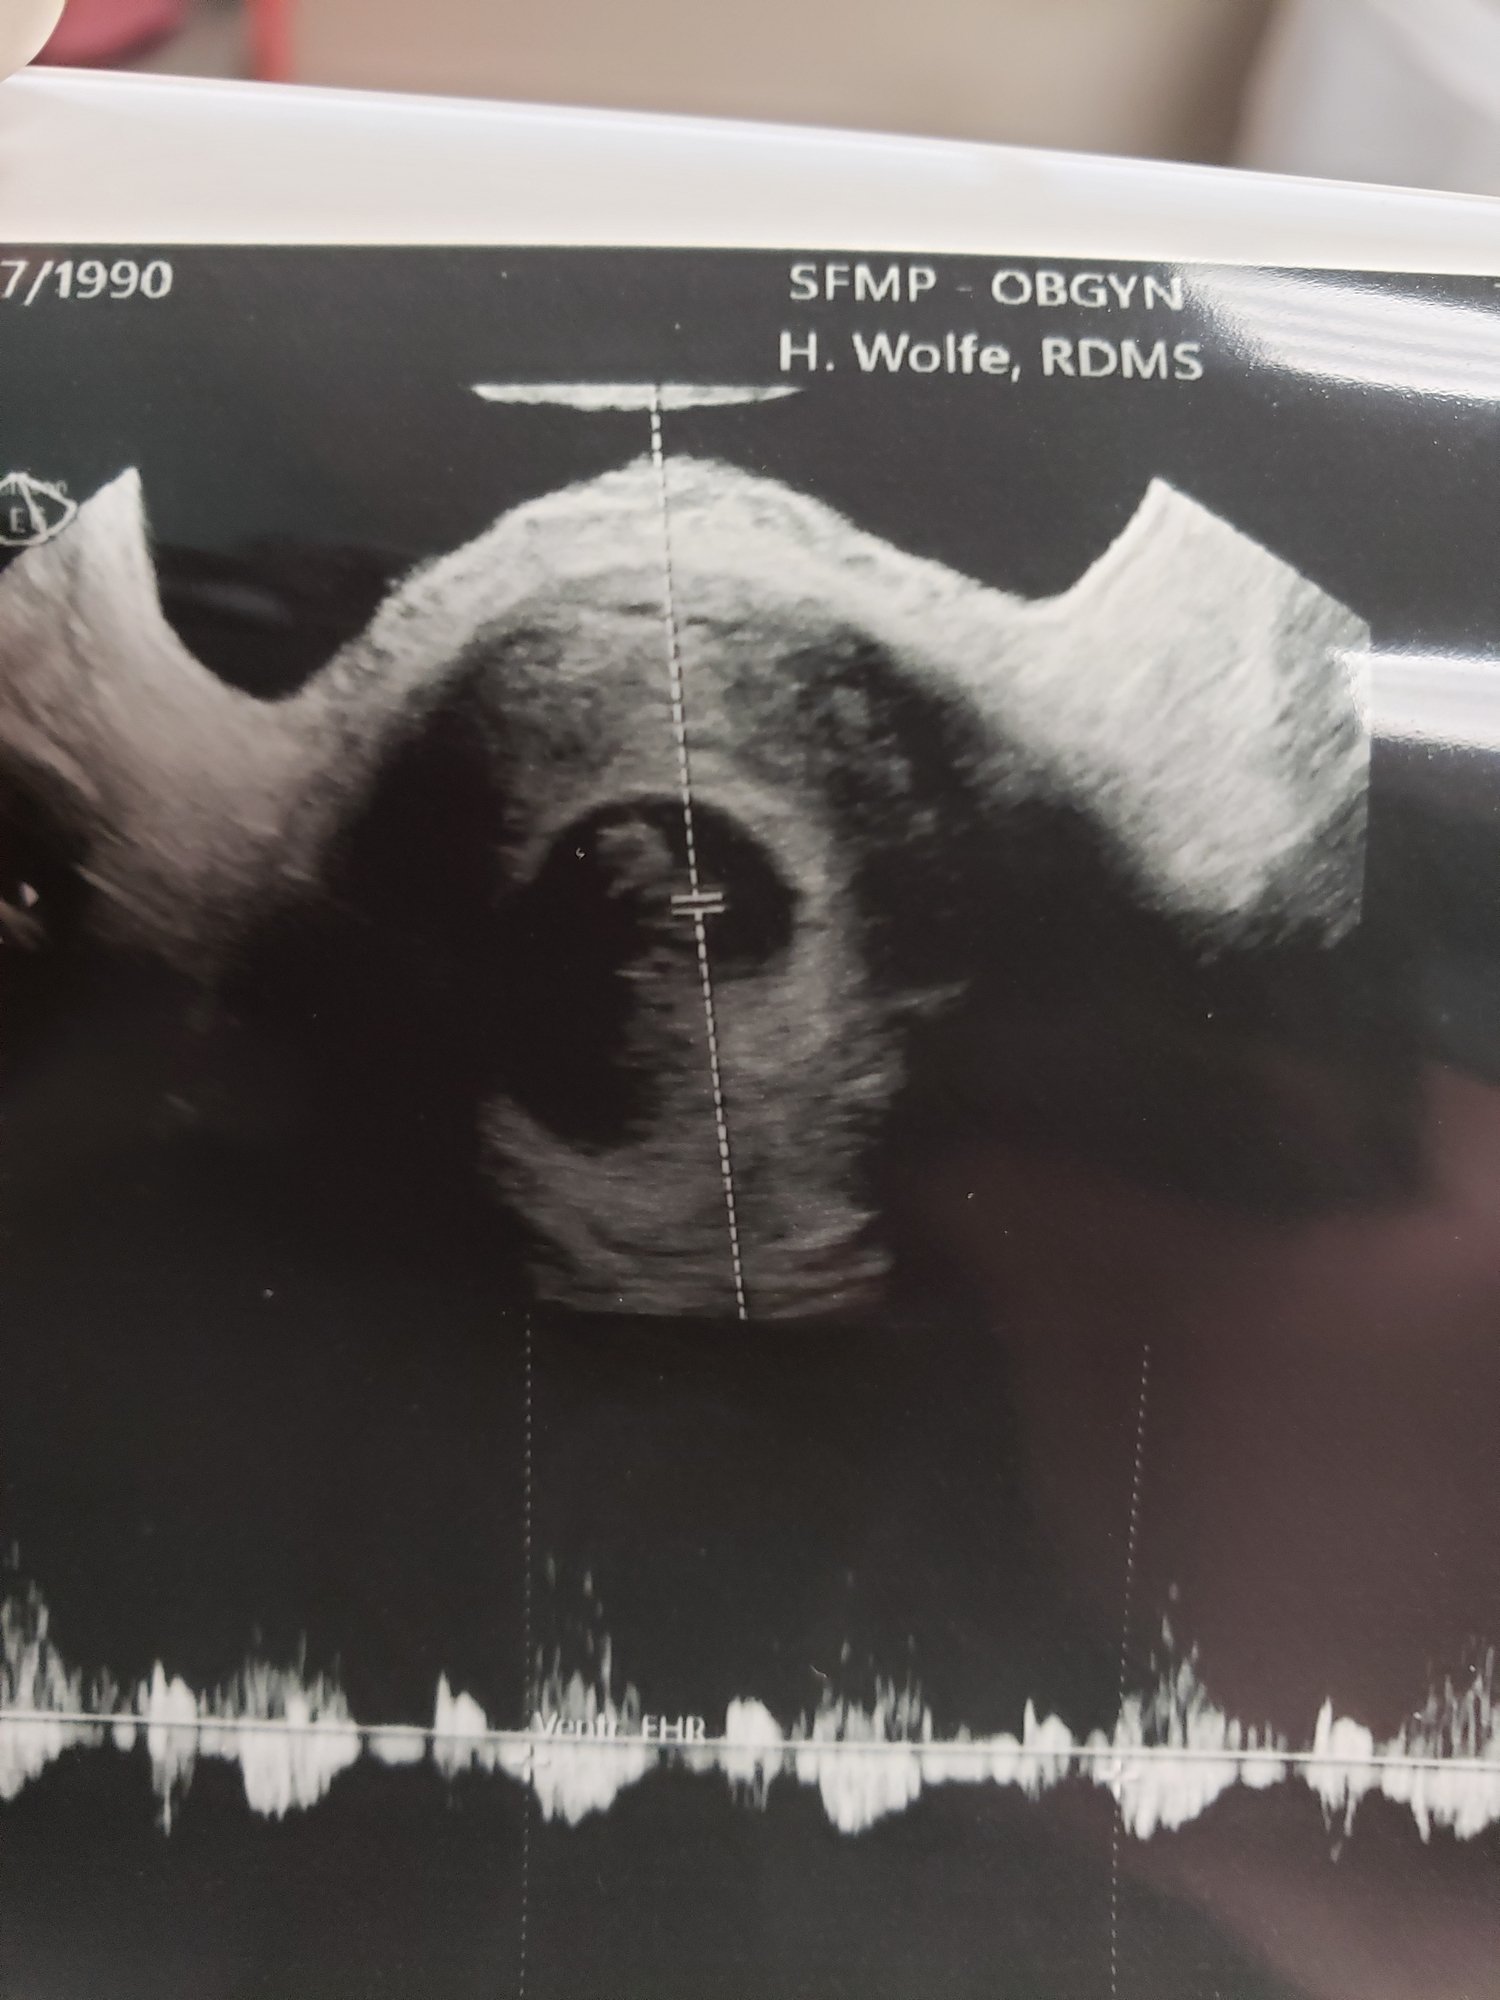

Well, today was quite a day! I started spotting brown blood last night so I went in. Ended up getting to hear baby’s heartbeat on a Doppler, then got an ultrasound. I don’t have a verdict on the spotting (we assume it’s my subchorionic hematoma resolving, fingers crossed!) but baby is growing right on track with a heart rate of 168 at 11w1 day. I’m so relieved and happy I got to see this little bub to make my week!